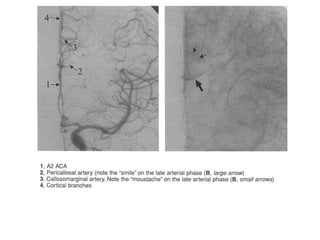

As setas indicam M2 contornando o

sulco circular da ínsula. A seta maior o

ponto silviano posterior, emergência da

artéria angular.

Segmentação da ACA

Artéria pericalosa

constantemente presente.

• Geralmente é a artéria formada pela bifurcação (próximo ao joelho

do corpo caloso) que dá origem as artérias pericalosas e

calosomarginal.

Artéria calosomarginal

• É definida pela artéria que cursa próximo ou no sulco

do cíngulo e que dá origem a dois ou mais ramos

corticais.